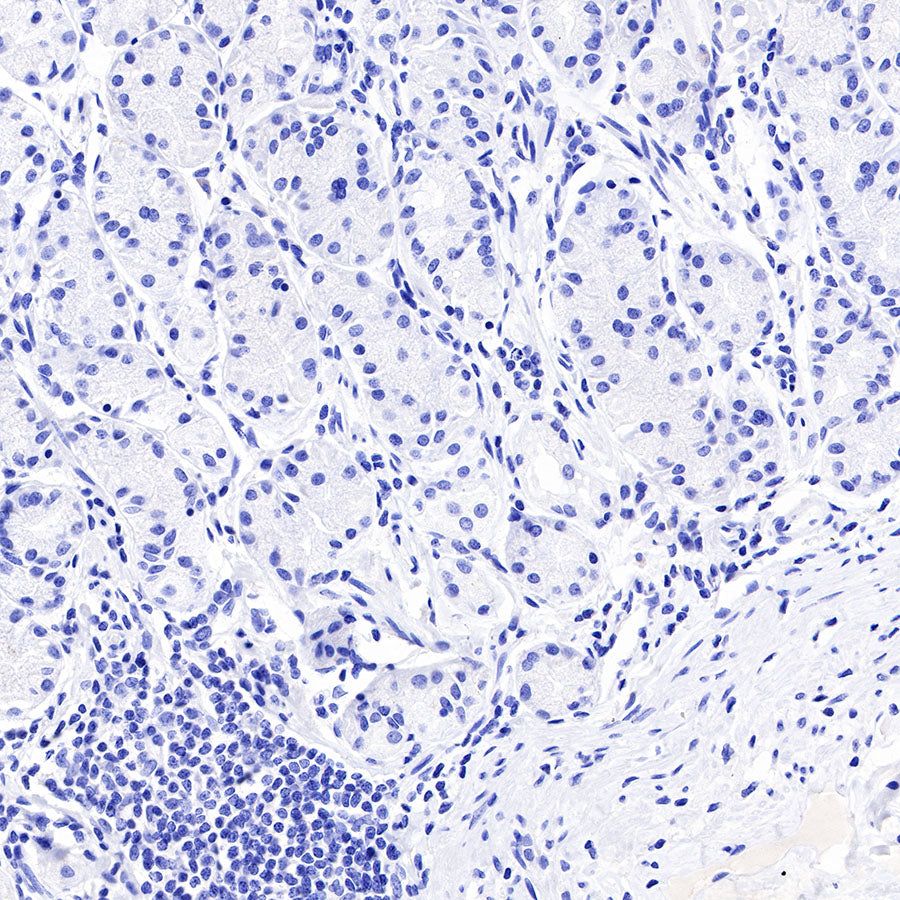

Negative control: IHC shows negative staining in paraffin-embedded human testis. Anti-PAPP-A antibody was used at 1/1000 dilution, followed by a HRP Polymer for Mouse & Rabbit IgG (ready to use). Counterstained with hematoxylin. Heat mediated antigen retrieval with Tris/EDTA buffer pH9.0 was performed before commencing with IHC staining protocol.